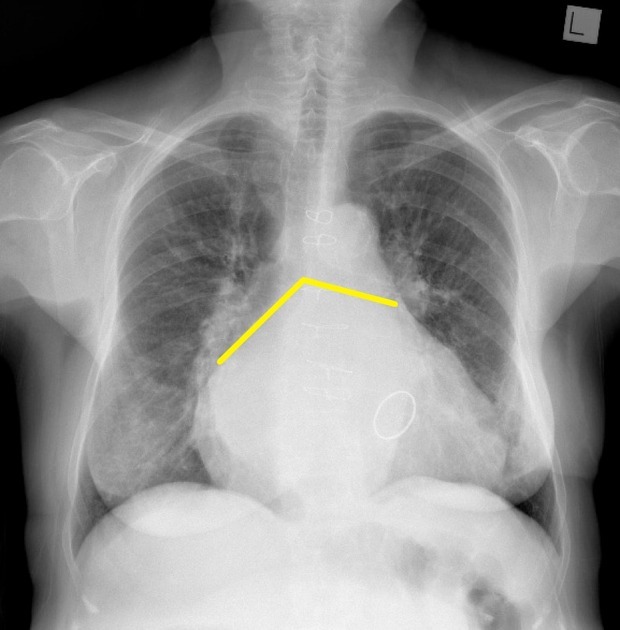

What is going on in this radiograph?

Left atrial enlargement

The potential space over where the left ventricle sits is where the atrium will expand into. You can also tell by the upward deviation of the carina, and the obtuse carinal angle